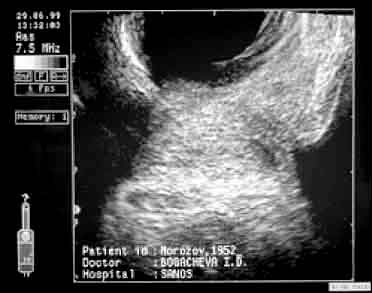

| То же после 15-дневного курса дренирующей терапии. Полное восстановление нормальной эхогенности и структуры ткани простаты. | |